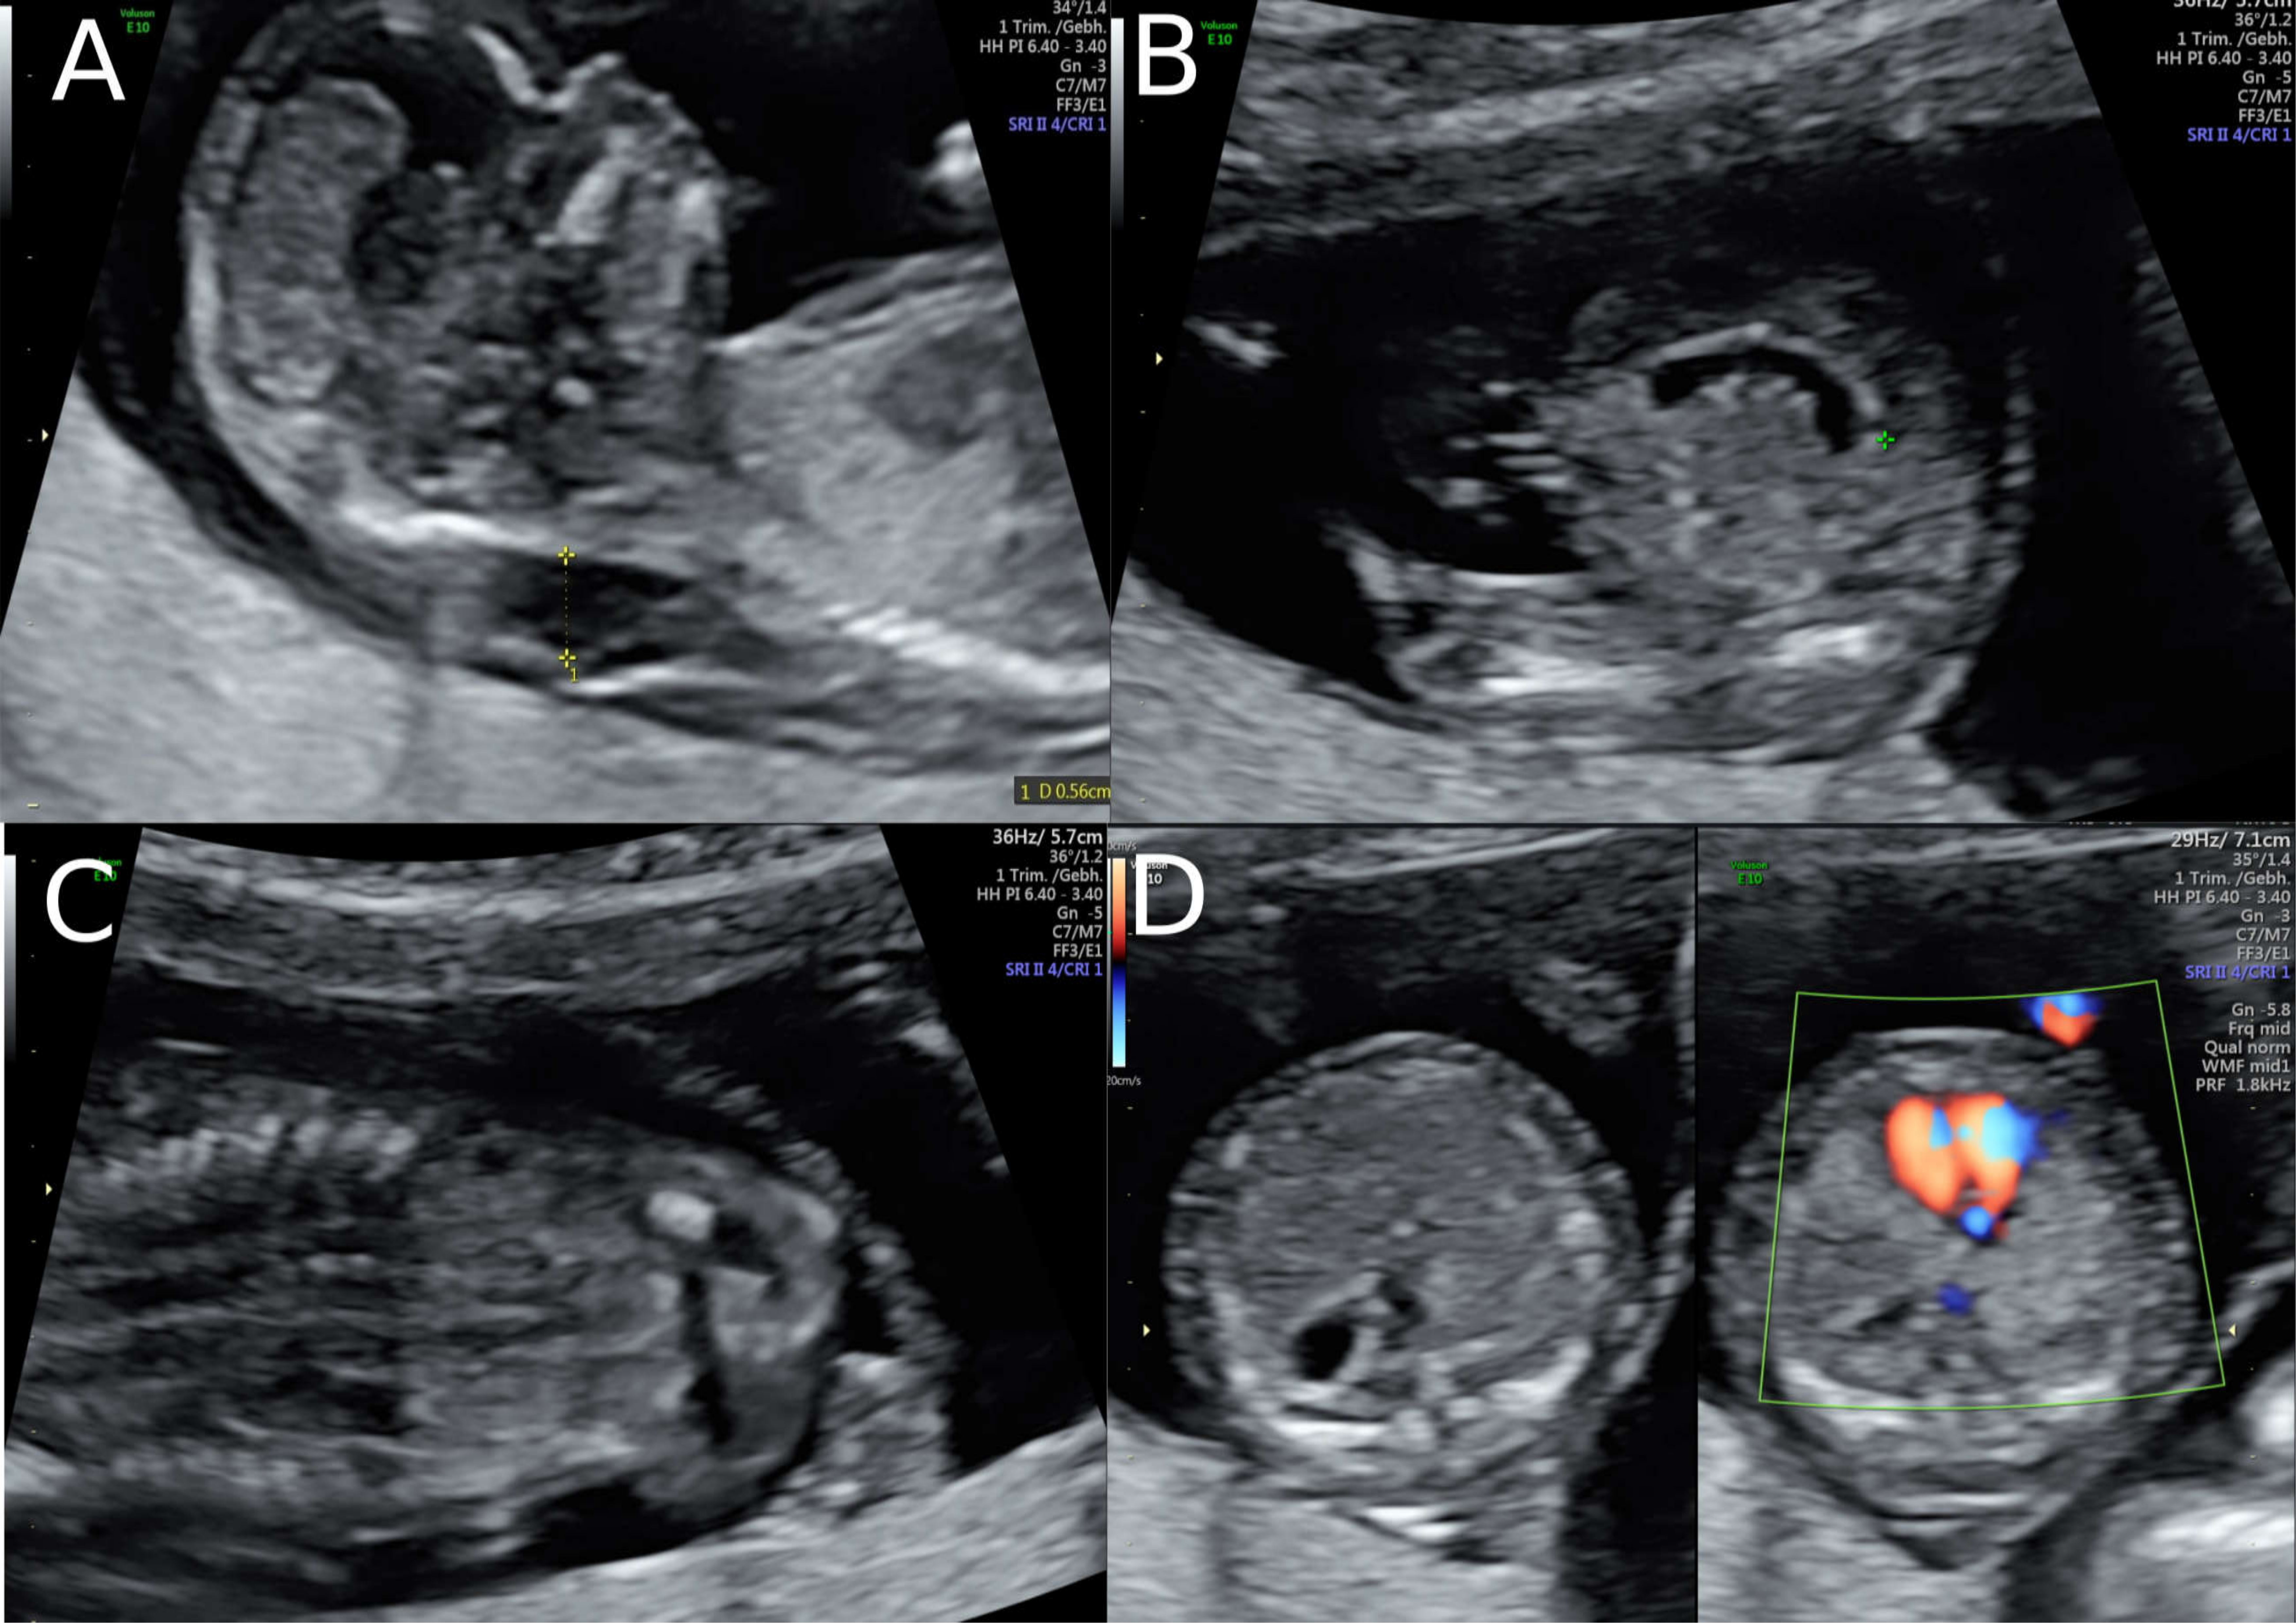

A 38-year-old women with a dichorionic-diamniotic twin pregnancy, after in-vitro fertilisation, attended routine first trimester screening at 13 + 4 weeks of gestation. One of the twins (fetus I) pair showed normal NT measurement and a low risk for chromosomal abnormalities, whereas the other twin (fetus II) presented an increased NT of 5.2 mm, the position of the fetal heart in the middle of the thorax, and hyperechogenic kidneys (Figure 1). At this stage, the patient declined invasive diagnosis. At 15 + 5 weeks of gestation, additional findings to the ones above, including hydronephrosis, skin oedema, and a right-sided clubfoot, have been observed. Subsequently, amniocentesis in the affected fetus was performed and revealed a 46, XY karyotype. Estimated fetal weight for both were average for the gestational age but abdominal circumference (AC) of the second twin was at the 95th percentile. At 22 + 0 weeks of gestation, the overall estimated fetal weight of fetus II was above the 95th percentile and a nuchal fold of 8.1 mm with general oedema of the skin was present. The ultrasound scan additionally showed a striking profile (Figure 2). All measurements (HC-AC-FL) were above the 95th percentile. A suspicion of left-sided diaphragmatic hernia as well as hyperechogenic kidneys, increased in size and polycystic appearance, and a hypoplasia of genitalia have been identified. Furthermore, the scan revealed a polyhydramnios (DIP 10 cm). Due to the polyhydramnios of fetus II, fetus I has been compromised in a similar process as twin-to-twin transfusion syndrome, although fetal development and amniotic fluid have been normal (Figure 3).

Whole exome sequencing revealed a hemizygous canonical donor splice site of the GPC3-Gene (NM_004484.3: c.175 + 1G > T) which causes SGBS. The Sanger sequencing of the mother could confirm that she is a heterozygous carrier of this mutation. There was no known family history of SGBS. After genetic counseling, the patient underwent fetal MRI to gain additional information as selective feticide has been discussed with the couple. The MRI revealed a conspicuousness of the diaphragm, i.e., diaphragmatic hernia versus eventration, with the stomach and the spleen being mostly positioned intrathoracic, as well as parts of the left and right lobe of the liver. Thus, consecutive moderate lung hypoplasia with a lung volume of 6.8mL on the right and 11 mL on the left side. Bilateral, multicystic kidneys with kidney parenchyma residual on both sides were described. Furthermore, the brain examination revealed accentuated ventricular width within the atrium area with especially frontal irregular ventricular confinement. All ultrasound and MRI findings are listed and compared to previous cases in Table 1.

Figure 3. Fetal MRI at 25 weeks of gestation: the fetal MRI picture reveals the massive polyhydramnios. Due to the polyhydramnios of fetus II, fetus I provided a similar picture like a stuck twin, as it is found in a twin-to-twin transfusion syndrome, although fetal development and amniotic fluid have been normal in the second twin.